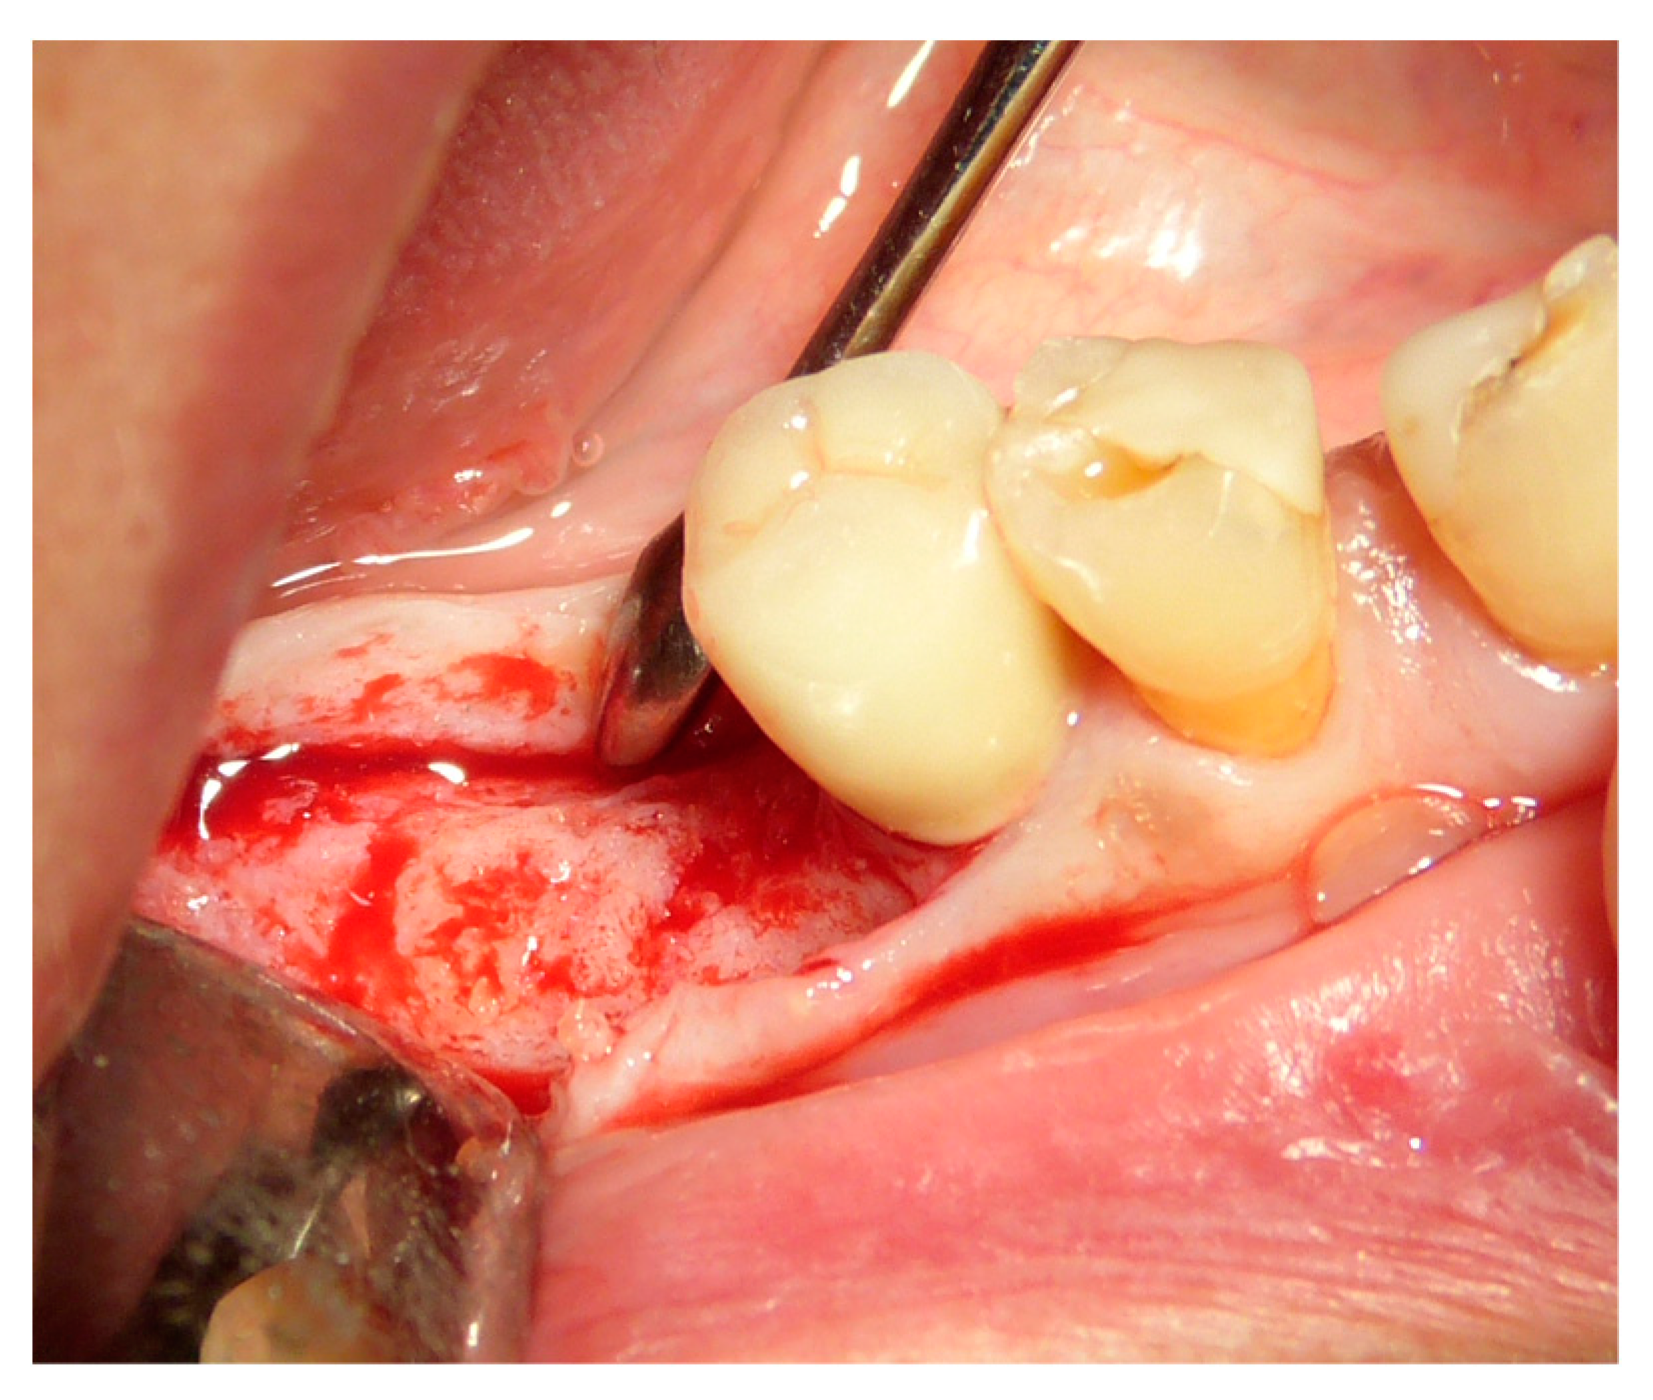

The vertical average defect was 9.16 mm, buccal lateral/palatal 7.0 mm, and mesio-distal 10.3 mm. The measurements were intraoperatively performed with a millimeter periodontal probe. The endodontic material mechanically cleaned before the tooth was placed inside the Tooth Transformer device. The endodontic material was removed using a drill bur with the attention to cut the canal in excess with the aim to remove all the cement. No surgical complications were registered. Pre and post-operative X-rays (section from CBCT) were collected from the same case (Figure 1, Figure 2, Figure 3 and Figure 4). After four months, 13 histological and histomorphometrical evaluations were performed (Figure 5). The Bone Volume/Total Volume average (BV%) was 41.47 (S.D. ± 11.51), the Residual Graft/Total Volume average (Graft%) was 16.60 (S.D. ± 7.09), and the Vital Bone/Total Bone average (VB%) was 21.89 (S.D. ± 9.72). No extraneous material (gutta-percha or cement) was detected in all samples (Table 3).

Figure 8. Ridge maintenance through the use of the extracted element and cover with a resorbable membrane.